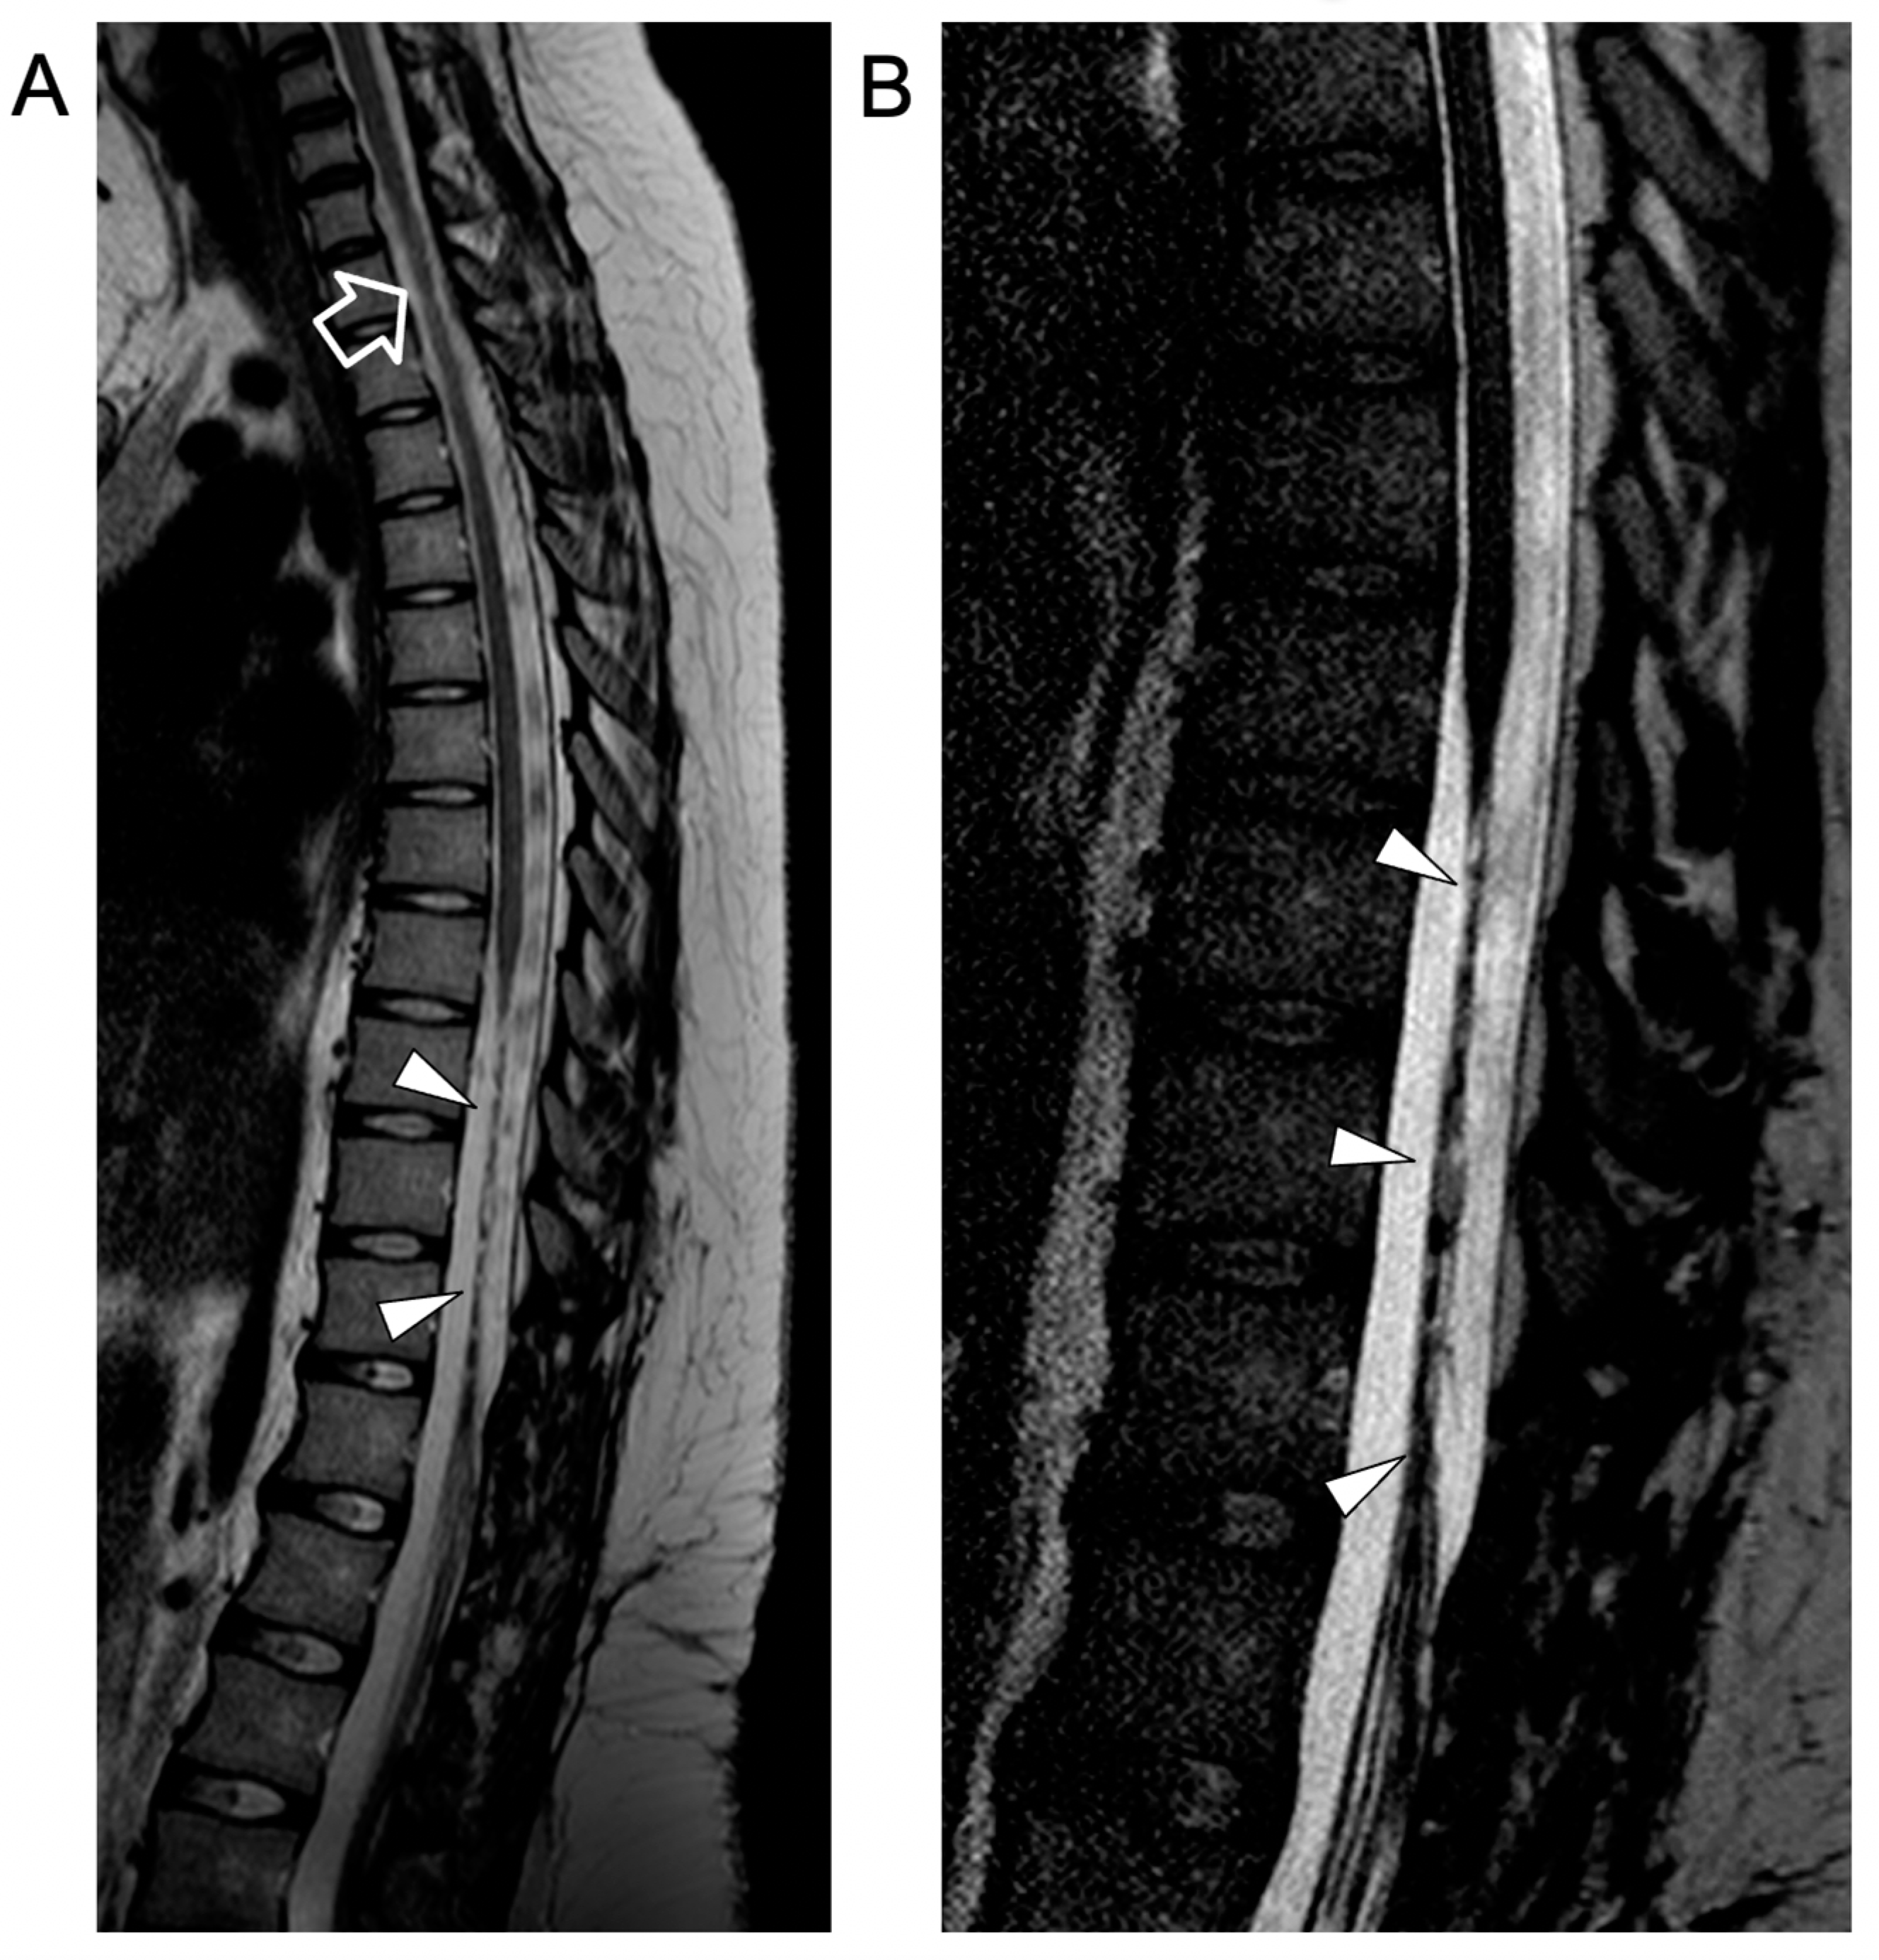

2. Case Report